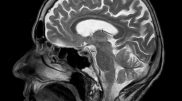

Eksperimentet për t’u mundësuar pacientëve të rikthejnë të folurit tregohen të suksesshme

Dy eksperimente të implanteve në tru tregojnë përparim të rëndësishëm në...